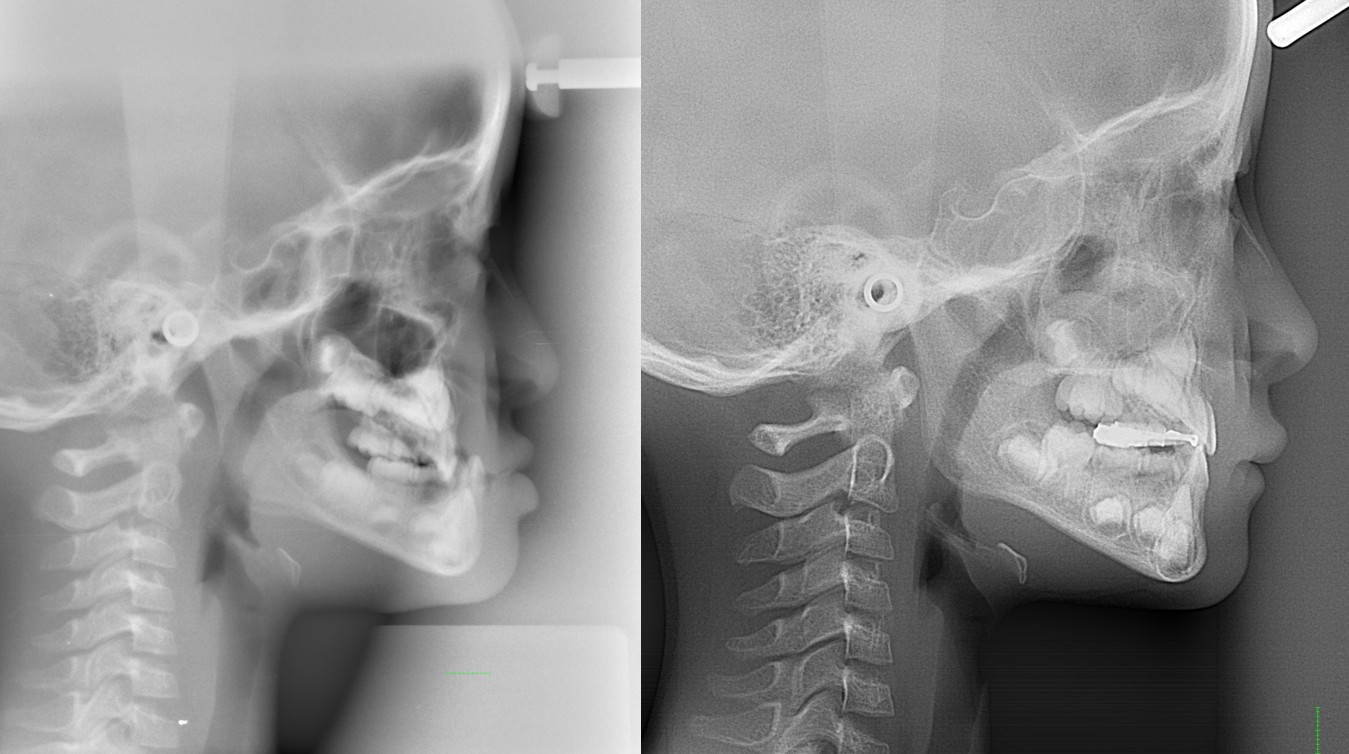

顎変形症

骨格性反対咬合・骨格性上顎前突・骨格性開咬・骨格性下顎側方偏位 などの外科矯正手術を必要とするもの

外見の改善を重要視するならば、矯正治療と外科処置を併用することにより適切な噛み合わせを回復したほうがよい場合もあります。

・主訴:下あごが出ている

・診断:骨格性下顎前突

・年齢:27歳

・使用した主な装置:マルチブラケット装置

・抜歯部位:なし

・治療期間:30か月

・通院回数:36回

・費用の目安:保険適応。保険矯正代金は、20万円くらい。症状・期間によってかわります。

・その他大学病院で外科矯正手術代金がかかります。